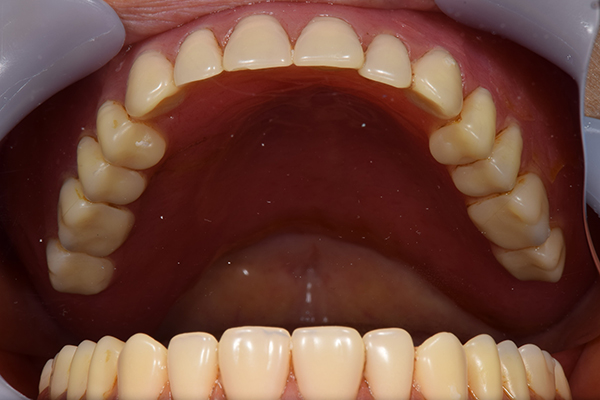

ケース4

(アタッチメントを用いた部分入れ歯)

右上のインプラント周囲炎で、その部分が痛いという患者様でした。 また奥歯で噛むことが難しかったため、前歯を使用することが多くなり、 前歯が前よりも前に出てきていることも気になっていらっしゃいました。

インプラント部以外にも歯周病が進行していましたので、歯周病の治療を行いました。 残念ながらインプラントと、1本の歯が残せなかったため抜歯を行いました。 その後、前歯の出っ張りを修正することと入れ歯の安定を図るため、残っている歯を全てかぶせ物にしていくことになりました。 写真中央は抜歯後に入れた治療用の入れ歯になります。 抜歯後歯ぐきが安定しましたら、入れ歯とかぶせ物の型取りを行いました。

噛み合わせチェックでしっかり奥歯で噛めるようにし、 歯を並べます。 その後、それに合わせて前歯を作っていきます。

最終的な入れ歯用の型取りをします。 シリコンで精密に型取りができました。

こちらが完成したかぶせ物と入れ歯です。かぶせ物にはアタッチメントをつけて金属のバネが見えない構造になっています。 入れ歯自体も金属を使用して、極力違和感がでないように、薄く作成しました。

お口の中に入れた状態です。 非常に見た目もよい出来となりました。 バネがみえないと見栄えが全然ちがいます。

年齢 70代・女性

主訴 奥歯のインプラントが痛い。

前歯がでてきた。

治療期間 6ヶ月

治療費 .メタルボンドクラウン7本:770,000円

.アタッチメント2個:220,000円

.義歯:550,000円

治療方針 ゆれてきたインプラントを抜去した後、歯周病の治療と、予後不良の歯を抜歯して、義歯を作成します。

抜歯後は治療用の入れ歯を作成し、ものが噛める様にします。

また前歯は、被せものをすることにしました。

治療内容 右上のボーンアンカードブリッジ(インプラントのブリッジ)部分がインプラント周囲炎になり、ぐらぐら揺れてきました。

そのため、インプラントを抜去した後、歯周病の治療と、予後不良の歯を抜歯して、義歯を作成していきました。

見た目が入れ歯とわからない様に針金のない、アタッチメントを使用した入れ歯を作成することにしました。

抜歯後は奥歯でものが噛める様に治療用の入れ歯を作成しました。

また前歯はフレアアウト(奥歯で噛めなくて前歯で噛む様になって、前歯が前に出てくる現象)していたため、患者さんの希望でかぶせ物をすることにしました。

特記事項 歯やインプラントを抜いた後は、2〜3ヶ月歯ぐきの回復を待ってから入れ歯を作るため、待機期間があります。その間、治療用の入れ歯を調整しながら使います。かぶせものをした後は歯がしみたり、場合によっては神経を抜く処置が必要になることもあります。